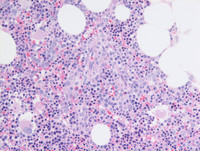

Figure 3: Marrow biopsy

Core biopsy is adequate for evaluation and is hypercellular for age with an estimated cellularity of 60% compressing scattered mostly normally megakaryocytes with very occasional dysplastic micromegakaryocytes with nuclear hypo-lobation and/or widely separated nuclei. There is preponderance of erythroid precursors (last image high power) which are maturing with intervening granulopoiesis including terminal segmented neutrophils and areas of abnormal localization of immature precursors (ALIP; third image bottom left). There is no morphologic evidence of lymphoma.

MDSRSMLDCore-biopsy

#00062010

#00062012

#00062011

#00062013